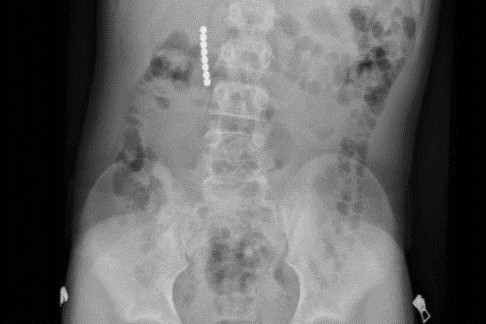

12-Year-Old Undergoes Emergency Surgery After Swallowing Magnetic Balls

Jerusalem, 8 July, 2025 (TPS-IL) -- A 12-year-old boy from northern Israel underwent emergency surge…